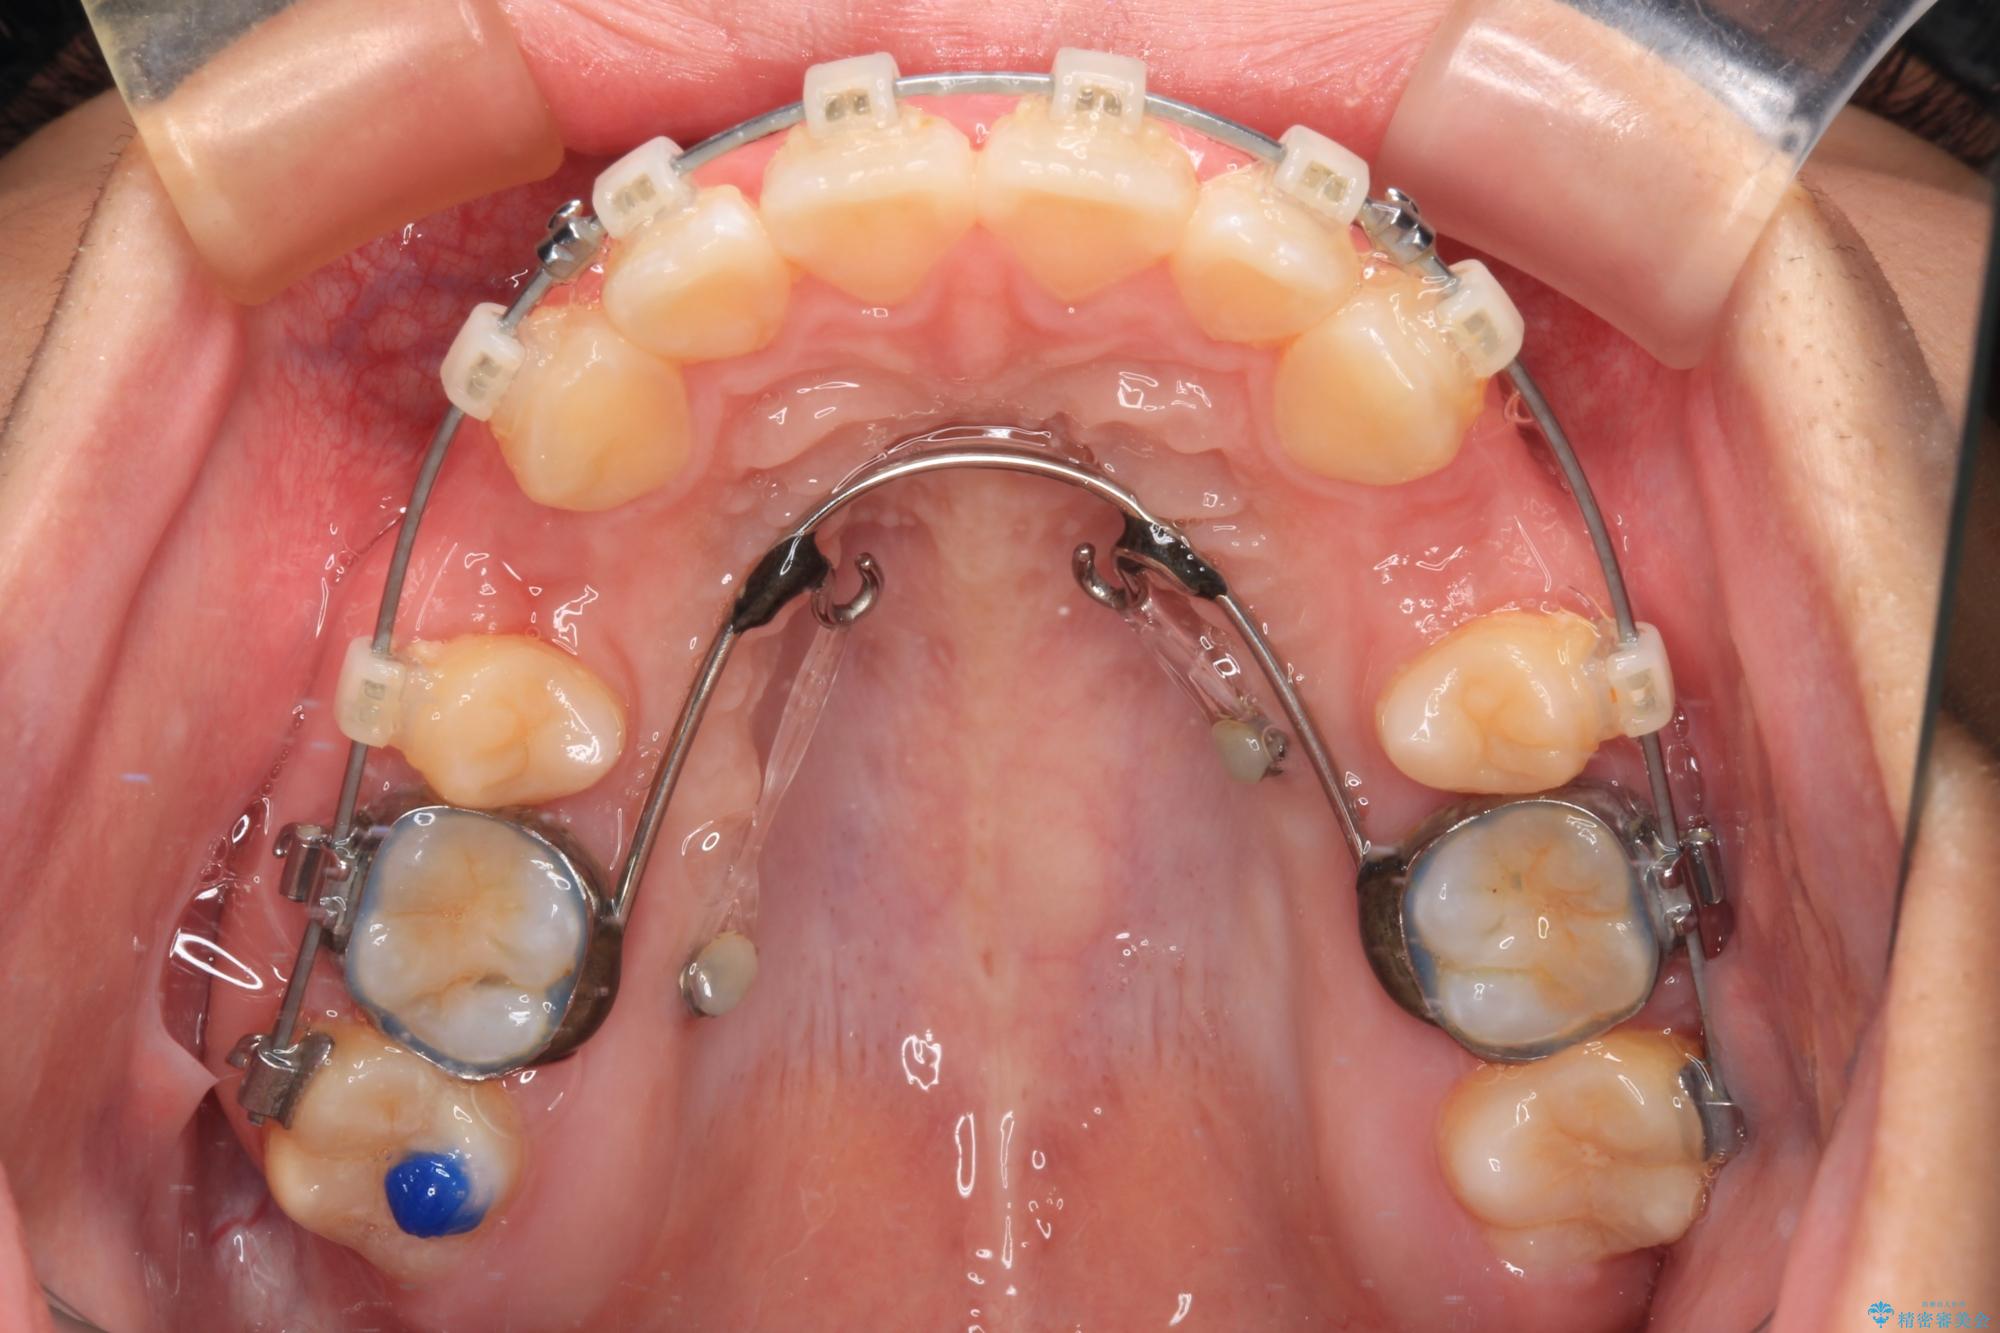

また、上顎歯列が下顎に対して前方位に位置していたため、補助装置を用いて上顎歯列を後方に移動させ、より積極的に口元を下げるようにしました。

- クリアブラケット